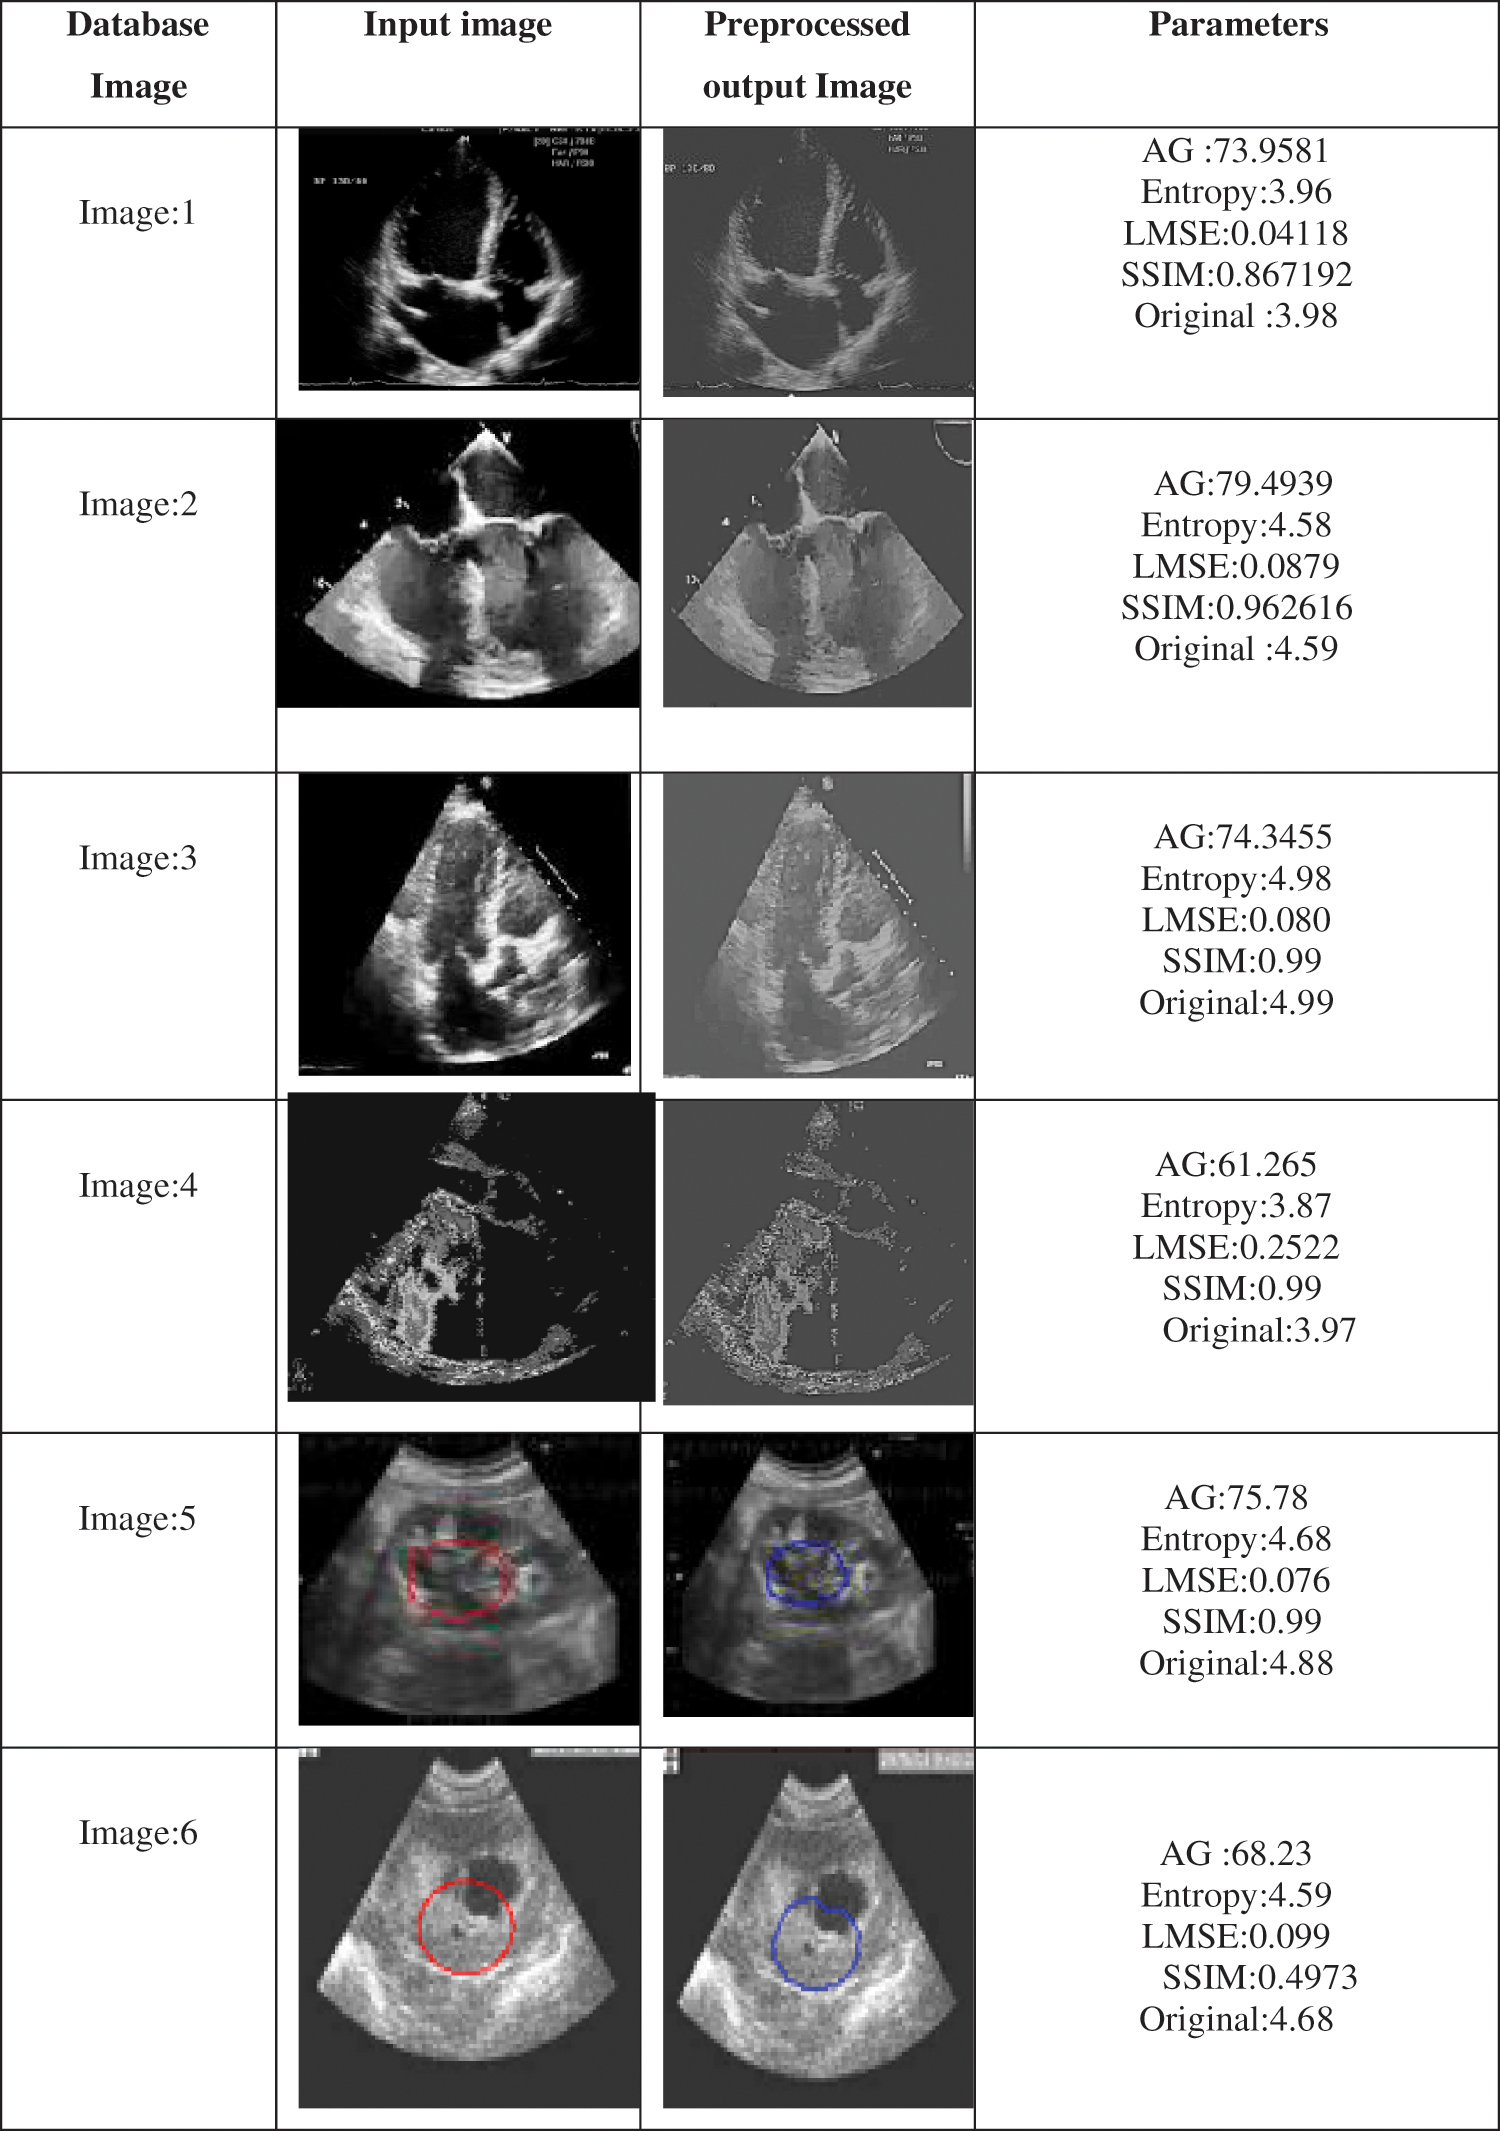

The effectiveness of the proposed method is tested using a set of echocardiographic images which are tested both in terms of quantitative and qualitative metrics. The performance metric used for quantitative analysis is Average gradient, entropy and SSIM. Entropy is defined by an Eq. (6) gives the information content in the image and also measures randomness whether close to either 0 or 1. The information content of the image is preserved by the proposed algorithm. Since Entropy is increased means no loss of information and from the tables, it is clear that entropy obtained using the proposed method is close to the original entropy of the image.

The average gradient decides the measure of improvement in image quality. It also decides how clear the image is. Where the increased value in AG indicates an increase in enhancement and also improvement in clarity achieved in the proposed method.

AG reflects the ability to express the details of an image and can be used to measure the relative clarity of the image. AG is calculated as shown in Eq. (16). Where numerator in the square root has first term representing partial derivative of image w.r.t ‘x’ and the second term is a partial derivative of an image

w.r.t ‘y’.

SSIM is a newer measurement tool that is designed based on three factors i.e., luminance, contrast, and structure as given in Eq. (17) to better suit the workings of the human visual system. This metric is widely used in image quality assessment.

If α = β = γ = 1 (the default for Exponents) then, l (x, y) is luminance, c (x, y) is contrast and s (x, y) is structure.

The proposed method uses filters for the enhancement of echocardiographic images using adaptive fractional order differentiation. The filter designed is capable of enhancing the image significantly and also preserves the structure of an input image. The proposed filter has the advantage of faster implementation of this method compared to other methods. This filter suitably adopts the fractional order of the masks concerning membership of the current pixel. The analytical test on the input echo images has proved and revealed enough the strengths and sustainability of the designed co-efficient.

If an order of the filter is integer order it is not suitable for images also when an order of the filter is fixed, in some parts of the image improvement is observed but other details in the image regions are affected. As given in Fig. 2 every image can be considered to be comprised of homogenous regions, details and edges. Higher orders are suitable for edges, low orders are for smooth regions and intermediate orders are for texture details in images. Hence fixed order filters when applied to the whole image the results are not good as the adaptive fractional order filter proposed in the paper. Each pixel in an image has a gradient magnitude which can be used to categorize regions or details or edges. However, a minimum value of gradient represents regions, a maximum value of gradient represents edges and intermediate values indicate details. Thresholds are computed using Eqs. (8) and (9). It is reflected from the tables that the proposed filter exhibited better results in comparison to state-of-the-art methods (as mentioned earlier in the paper) by not only increasing AG value but also information content in images is preserved as indicated by the value of entropy being close to the original value of information in images. Hence it can be concluded that the adaptiveness of the filter results in improvement and enhancement by appropriately selecting fractional-order for edges, details and regions as given by Eq. (14).

After partitioning the image into three regions accordingly order of the filter is selected for pixels in different regions and an enhanced image with improved contrast is suitable for physicians’ inaccurate diagnoses. Tabs. 1 and 2 show the proposed algorithm is a better method of image enhancement.

The desired algorithm is also tested with the non-medical image database, and its comparative analysis is done with the existing and proposed algorithms as shown in Figs. 4 and 5 and its tabulated values are as shown in Tab. 2. For analysis, it is considered only with three types of test input images, Lena, Checkerboard and US image. Fig. 6 shows windows exhibiting the variation in the MSE performance metric and can be seen how the error becomes minimum almost near to zero which is a requirement for achieving enhancement and Fig. 7 gives a summary of tested images from the dataset.

Figure 7: Results summary for the tested database with parameter metric of qualitative analysis